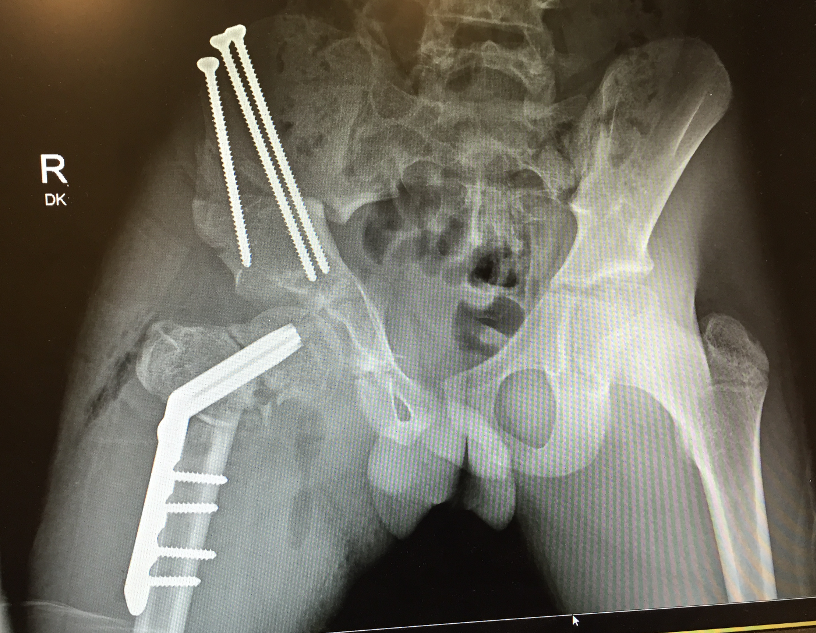

Aitken's Classification

Class A

- short femoral shaft with coxa vara

- head of femur present, neck may be absent early

- adequate acetabulum

- bony connection between head & neck present at maturity

- may be pseudarthrosis at point of connection

1. Pseudoarthrosis

2. Instability of the hips

3. Coxa vara

1. Stabilize pseudarthrosis with IM Rod

2. Hip stabilisation

- pelvic osteotomy

- femoral osteotomy

1. Realign Coxa Vara

- subtrochanteric osteotomy